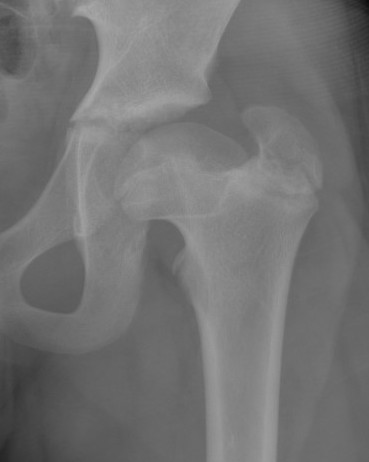

Waldenstrom Stages

1. Initial

Duration : 3- 6 months

Xray

- may be normal

- small, sclerotic epiphysis

- joint space widening

- increased density of ossific nucleus & cessation of growth

2. Resorption / fragmentation

Duration : 6/12

XRay - Fragmentation of Physis

3. Reossification

- Better defined shape

- Return of bone density

4. Remodelling

Xray - May have flattening of the head and neck

Herring Lateral Pillar

AP xray when disease in fragmentation / divide femoral head into 3 pillars